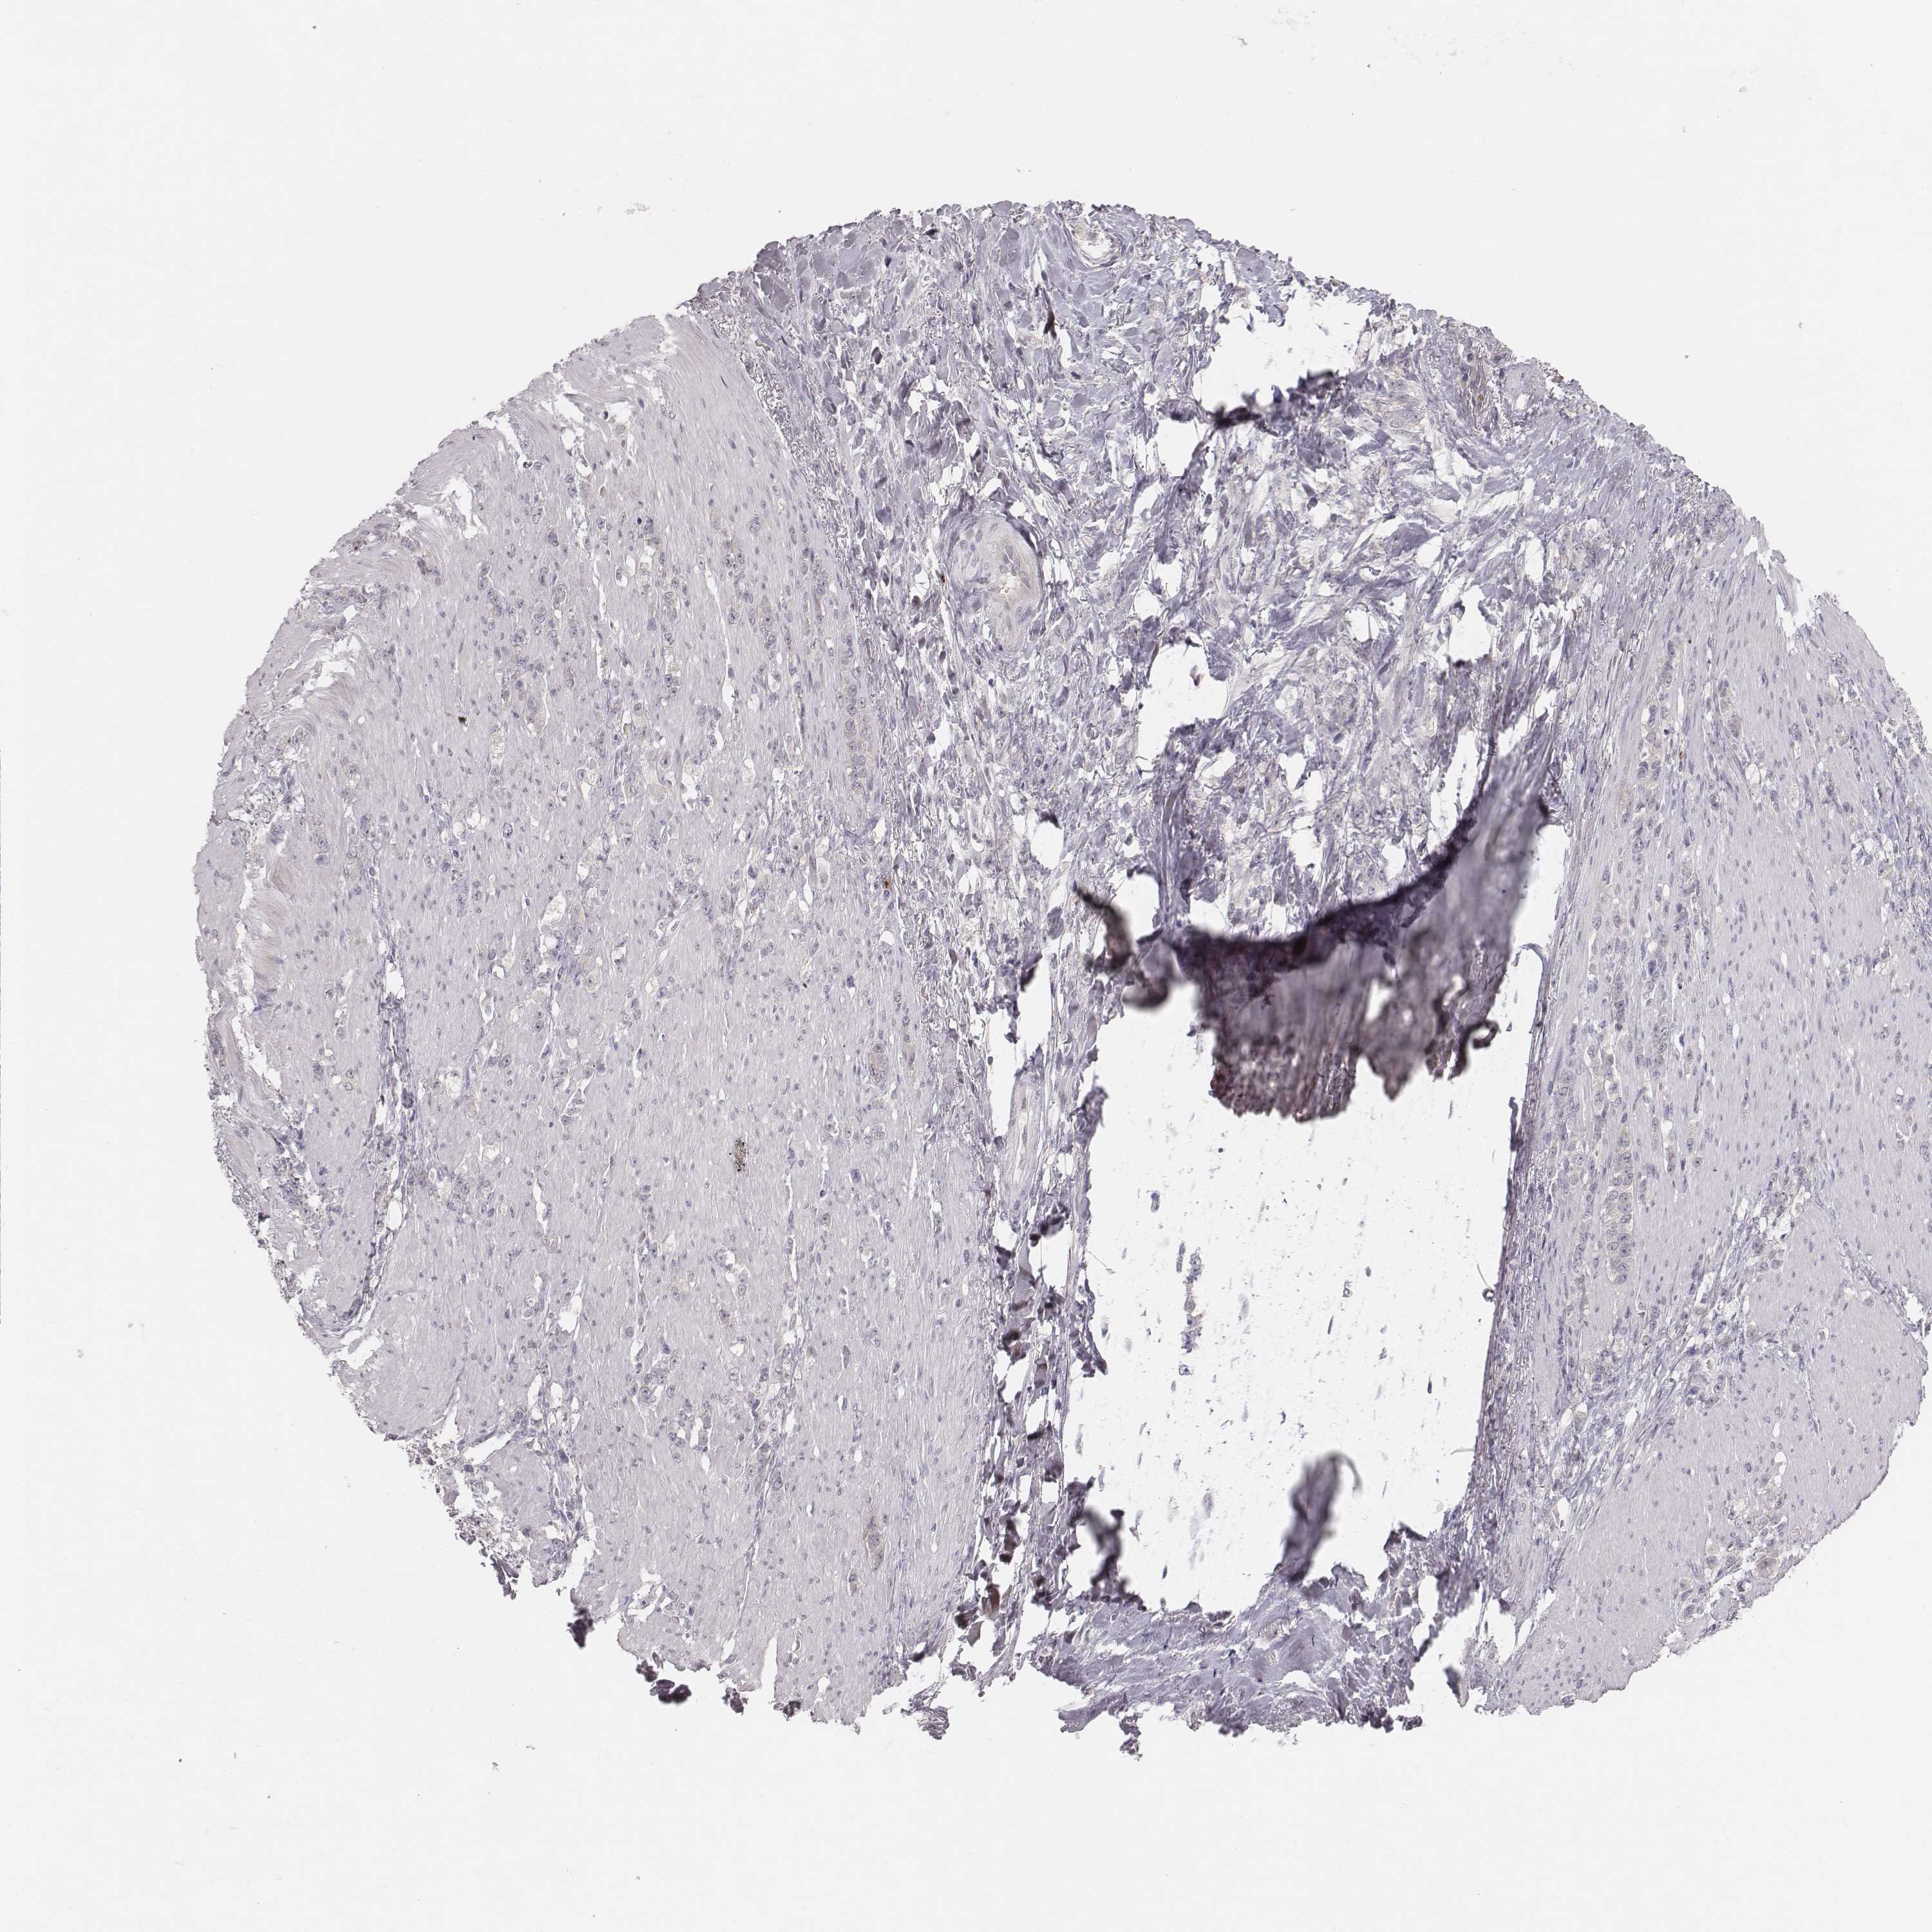

STOMACH CANCER - Protein expressioni

A mouse-over function shows sample information and annotation data. Click on an image to view it in a full screen mode. Samples can be filtered based on level of antibody staining by selecting one or several of the following categories: high, medium, low and not detected. The assay and annotation is described here.

Note that samples used for immunohistochemistry by the Human Protein Atlas do not correspond to samples in the TCGA dataset.

Antibody stainingi

Antibody staining in the annotated cell types in the current human tissue is reported as not detected, low, medium, or high, based on conventional immunohistochemistry profiling in selected tissues. This score is based on the combination of the staining intensity and fraction of stained cells.

Each image is clickable and will lead to virtual microscopy that enables deeper exploration of all samples and also displays staining intensity scores, fraction scores and subcellular localization as well as patient and tissue information for each sample.

Antibody HPA043261

Antibody HPA043264

Antibody HPA044028

Adenocarcinoma, NOS